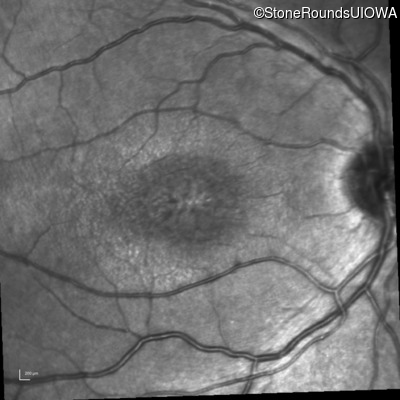

Infrared Fundus Photograph - Left - 20/50 -2

Exemplar